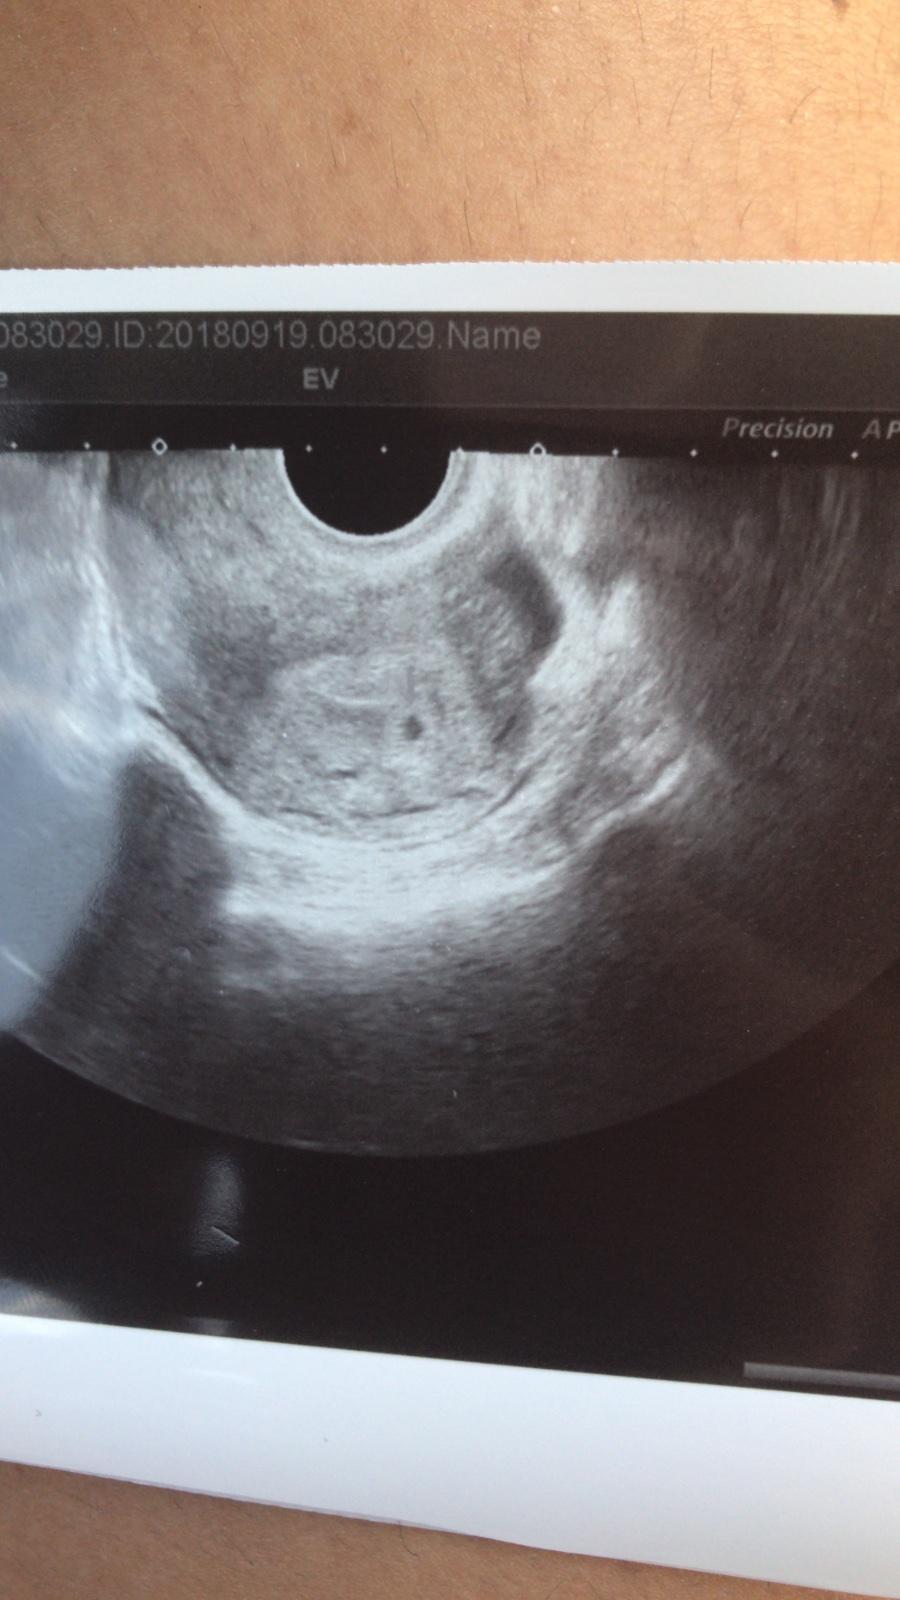

@saminomimino 5+0 a odpovídá, on to nepribližoval, byla jsem tam kvůli potvrzení že je v děloze.

Ahoj Holky, tak dnes jsem byla na gyn. Je to v děloze, dle MS jsem 5+6, dle UZ 5+3 a přítomen gestační a žloutkový váček🙂. na fotečku jsem úplně zapomněla, ale hlavně že to je, kde má být a odpovídá🙂. Další kontrola za 14 dní, prý už vystaví těhotenskou průkazku.